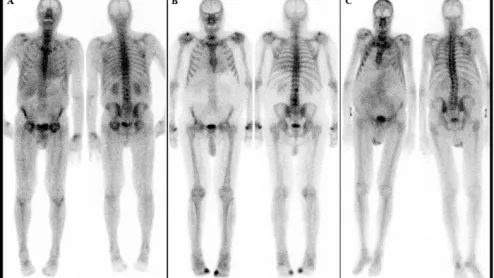

The REVEAL study has been assessing the sensitivity and specificity of iodine 124 evuzamitide (I 124 evuzamitide), a PET agent capable of visualizing signs of cardiac amyloidosis on imaging.